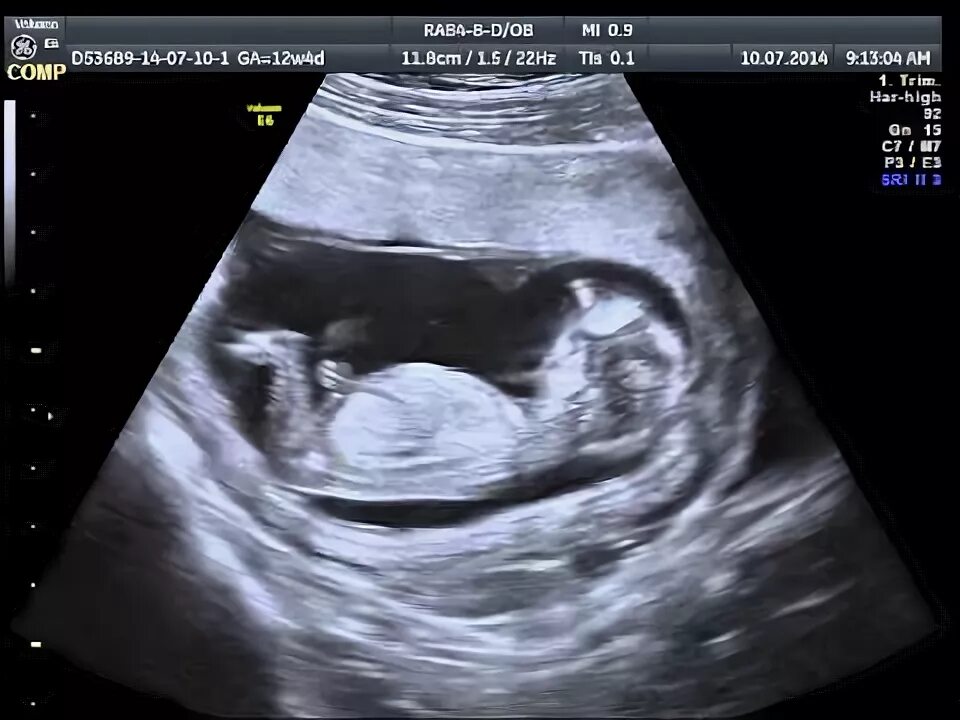

13 недель как выглядит малыш